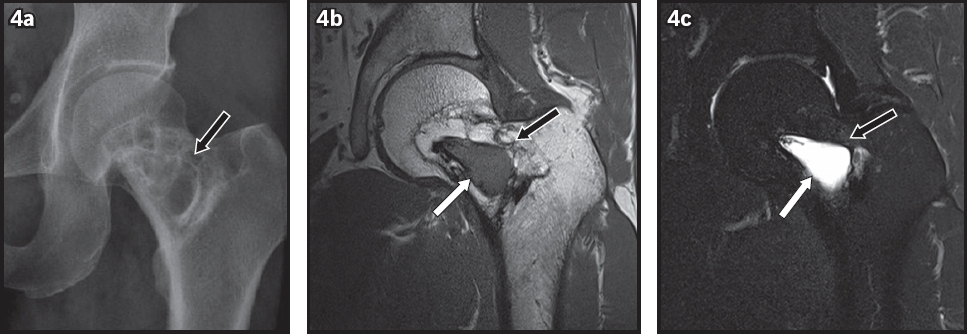

Fig. 4

Stage 3 intraosseous lipoma of the femur. (a) Anteroposterior radiograph shows a multiseptated lucent lesion in the left femoral neck (black arrow), which may be mistaken for fibrous dysplasia or an aneurysmal bone cyst. (b) T1-W and (c) T2-W fat-saturated MR images show the lipomatous lesion (black arrows in b & c) in the femoral neck with a cystic component (white arrows).